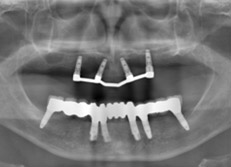

大掛かりなインプラントによる治療

この症例は、すべての歯を失った口腔内をインプラントで治療した例です。

治療前のパノラマエックス線写真。歯がほとんど残っていませんし、残っている歯もほとんど使えません。

パノラマエックス線写真

術後のパノラマエックス線写真